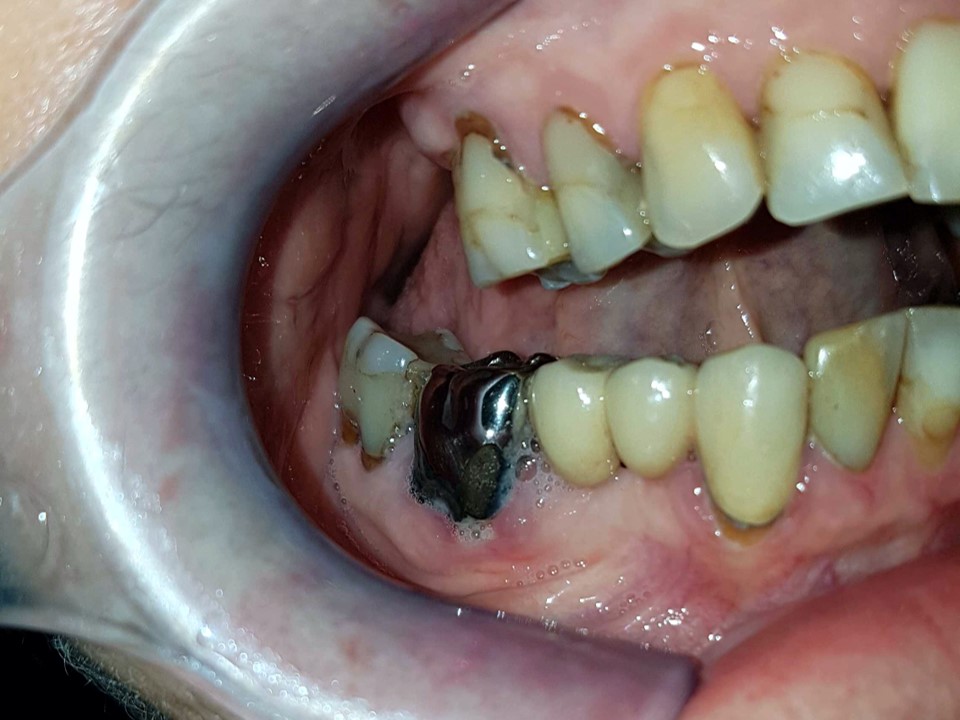

Sofern der Zahnhals freiliegt sind die Zähne dunkel verfärbt (Schwarz ist die Farbe des Todes). Bei diesem Zahn ist auch noch eine Silberkrone zu erkennen, was unter Umständen die Giftigkeit des Zahnes noch weiter erhöht.

Bei diesem überkronten wurzelbehandelten Zahn ist der dunkle abgestorbene Teil wieder gut zu erkennen. Aber hier soll noch etwas hervorgehoben werden. Das Zahnfleisch welches den Zahn umrandet ist deutlich gräulich sulzig verändert. Diese ist häufig auf die Einwirkung der Bakterien und Toxinen zurückzuführen.